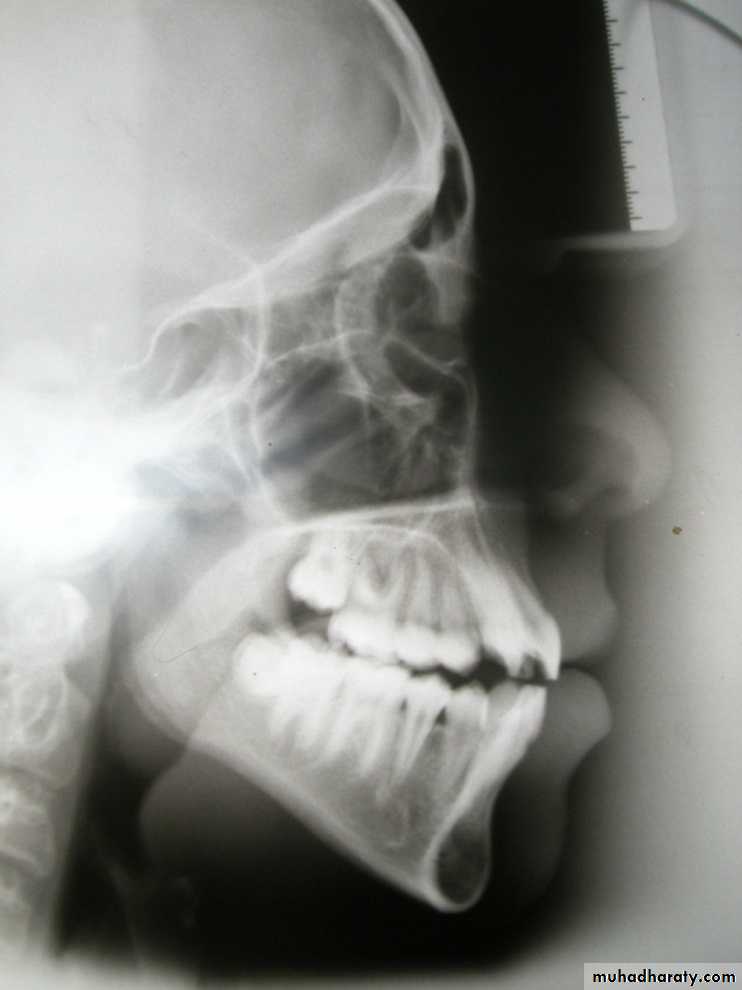

Cephalometric lines of reference

3. Sella - Nasion plane:

S - N

4. De Coster’s line:

The floor of the anterior

cranial base, from ethmoid

bone to sella turcica

5. Maxillary line:

ANS - PNS